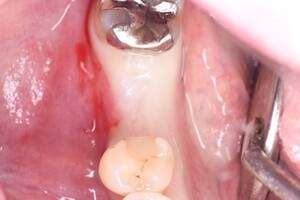

口腔内写真

- Befor

- After

| 年齢 | 50代・男性 |

| 主訴 | 部位:左下6番7番 主訴:左下奥歯腫れて痛い。 |

| 治療内容 | 左下6番抜歯、左下6番7番骨造成、インプラント埋入 |

| 治療費 | 合計:1,232,000円 ・内訳 診断料:55,000円 サージカルガイド2本:66,000円 GBR:110,000円×2本 埋入料:165,000円×2本 静脈内鎮静麻酔:77,000円 2次OPE:22,000円×2本 仮歯:55,000円×2本 上部構造(フルジルコニア):165,000円×2本 (2023年1月現在) |

| 治療期間 | 約8ヶ月 |

| 治療方針 | 元々支台歯に負荷がかかりやすいとされている延長ブリッジを抜歯し、1本単体でしっかりかめるようにインプラントを2本埋入した。骨吸収も進んでいたため、※GBR法で骨造成を同時に行った。 治療と並行して、全顎的な歯周病治療も行い、今後は歯周病が進行しないよう、こまめにメンテナンスに通っていただく。 |

| 特記事項 | ※1 GBR・・・骨再生誘導法。骨の高さや厚みを人工骨や人工膜などを使用し再生する方法 |

| 担当者所見 | 6番は歯根分割された被せ物が7番の欠損部との延長ブリッジとされており、強い咬合と歯周病も相まって負荷がかかり動揺し、歯として機能しなくなったため、抜歯となった。 |